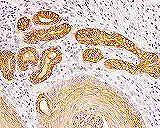

免疫染色(酵素抗体法)は細胞に存在する抗原(蛋白)を酵素反応により可視化させ、検出す る方法です。(いろいろな蛋白が組織内のどの細胞に存在するか確認することができます。 |

病理分野では重要な染色方法となっています。 断に活用しています。 |